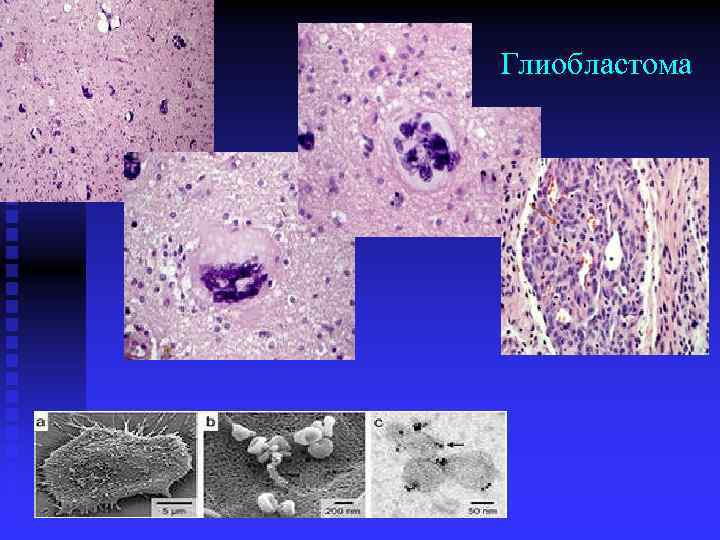

Микрофотографии гистологии глиобластомы головного мозга